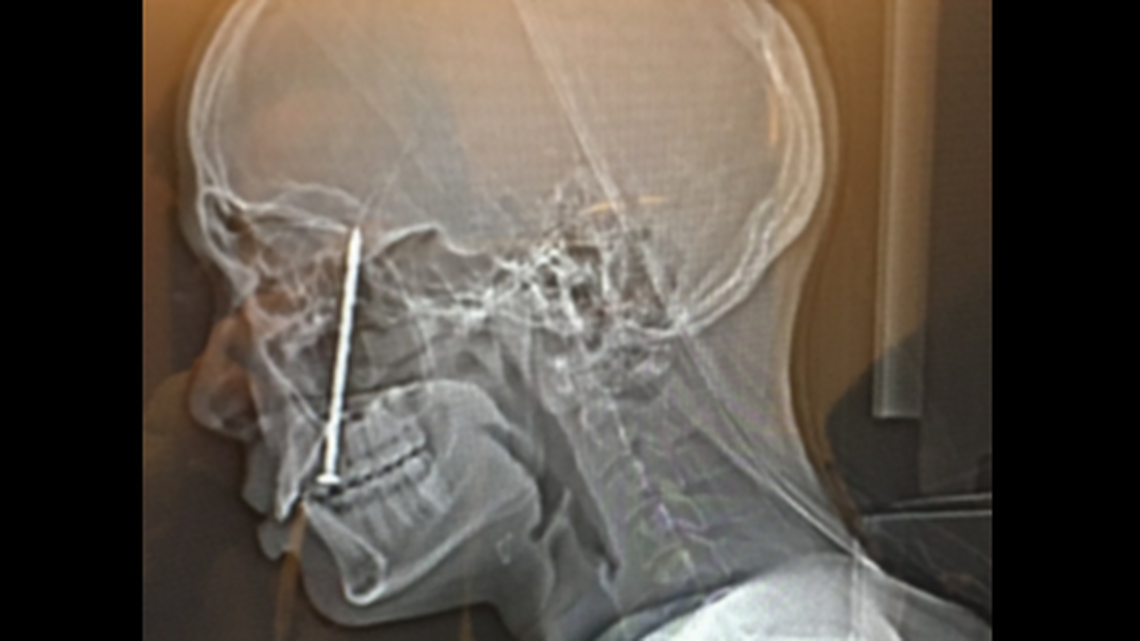

A CT scan of Timothy Kahae’s skull on Nov. 15, 2021, shows the nail in his head, according to the lawsuit.

A CT scan of Timothy Kahae’s skull on Nov. 15, 2021, shows the nail in his head, according to the lawsuit. Complaint

Timothy Kualii Kahae, who is now 28, needed emergency surgery to remove the nail that was lodged in the base of his skull in an incident that left him “permanently scarred,” a complaint filed Nov. 3 in federal court says.

This is when the nail gun misfired and simultaneously shot out two nails — one of which ricocheted off the other nail, launching it upward and into Kahae’s tongue and skull, the complaint says.

He ultimately had to wait a day for the surgical procedure to remove the nail, repair wounds to his tongue and the roof of his mouth, and more, the complaint says.